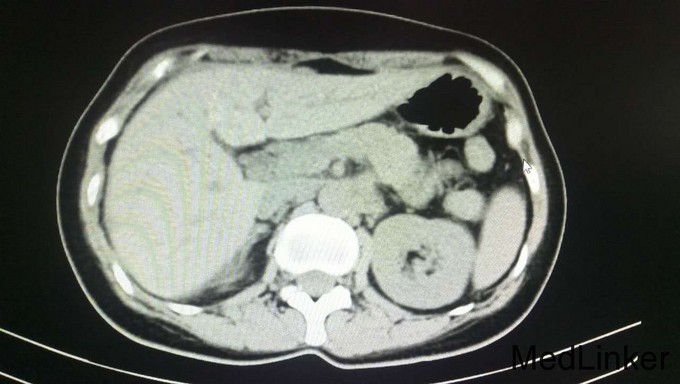

查体:腹平软,全腹部未扪及明显包块,全腹无压痛、反跳痛,右侧上中腹部可见一长约12cm的手术瘢痕,愈合良好,肝脾肋下未触及,墨菲氏征阴性,移动性浊音阴性,肠鸣音正常,无血管杂音。双肺呼吸音清,未闻及干湿性啰音,心脏听诊律齐,各瓣膜区未闻及明显病理性杂音。四肢查体无明显异常。 辅查:术后病理示:右半结肠中分化腺癌,部分为粘液腺癌,浸润肠壁全层,并侵犯神经组织,胰腺旁淋巴结见癌组织浸润并侵犯神经组织。2015年4月全身PET/CT检查示:右半结肠吻合口未见占位,纵膈1L组、肝门、腹膜后、右侧结肠旁沟淋巴结转移瘤,肝内转移瘤,胰头下方软组织转移瘤,双肺多发小结节,不排除转移瘤。2015年6月复查CEA:1353ng/mL,CA199:9674u/mL(较前明显升高)。其余重要影像学检查如下图所示: